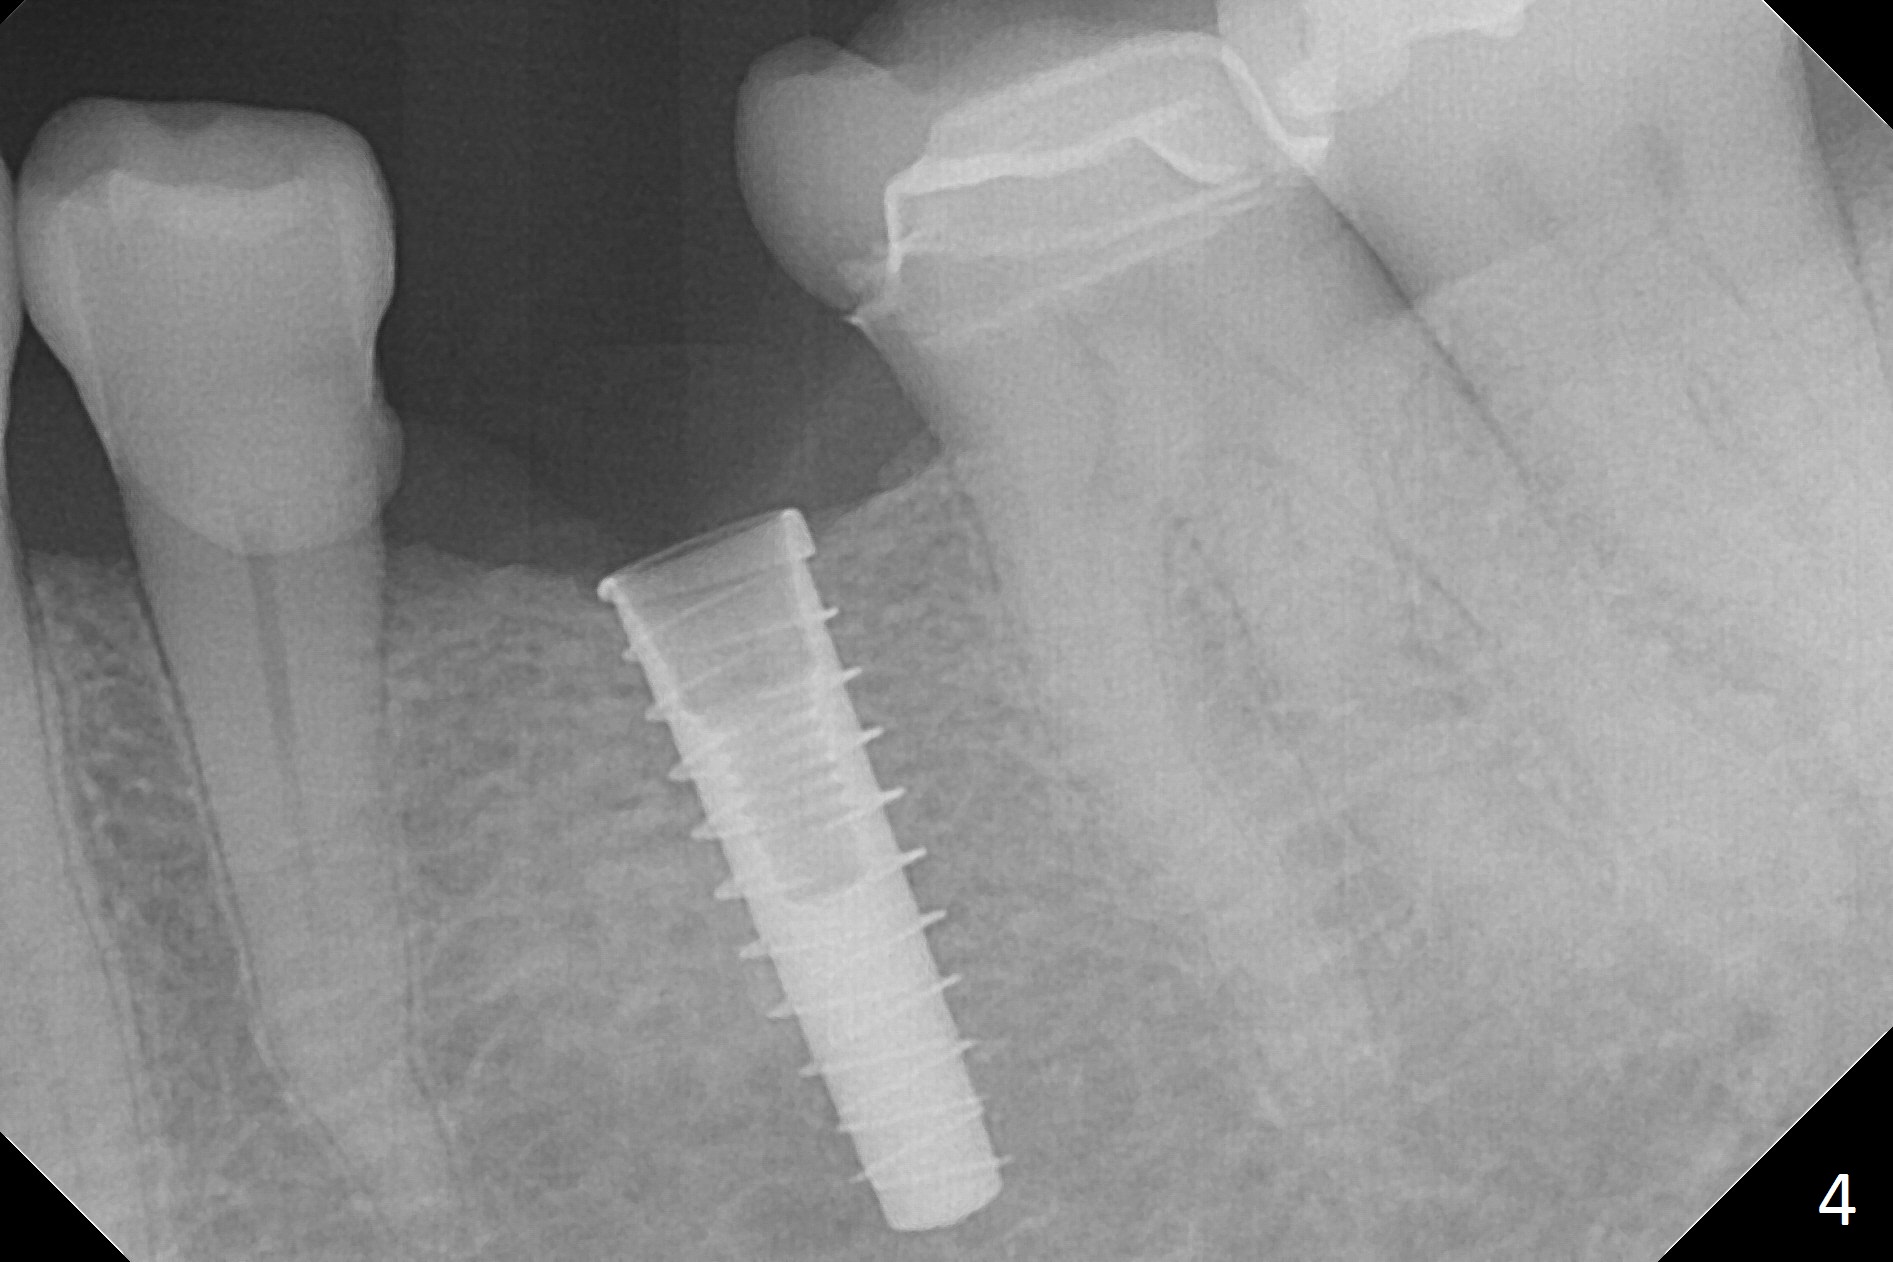

Initial osteotomy with 1.6 mm drill for 11 mm seems to be distal (Fig.1).  The trajectory should be changed as shown by the black line in Fig.2; the drawback would be close to the Mental Loop (red line).  Fortunately the trajectory is changed, but not so much as to be close the Loop when a 4x11 mm dummy implant is placed (Fig.3).   When a 4x13 mm IBS is placed with 46 Ncm, there is clearance from the Loop (Fig.4-6).  In fact there is no postop paresthesia.  The main point is no block anesthesia.  Infiltration anesthesia is administered with 34 mg Xylocaine with 17 mcg Epinephrine.  The patient experiences dull pain when the implant is placed (Fig.4-6).  After further anesthesia with 68 mg Septocaine, 17 mcg Epinephrine, the implant is torqued for a few turns (still with some discomfort).  Finally autogenous bone with Osteogen is placed around the implant following placement of a 4.5x4(2) mm abutment.  To reduce anxiety, a shorter implant should have been used. The patient complains of cold sensitivity in the lower left quadrant 4 months postop (Fig.7): the implant apparently close to the Mental Loop.  Without an immediate provisional, the gingiva around the abutment is healthy.